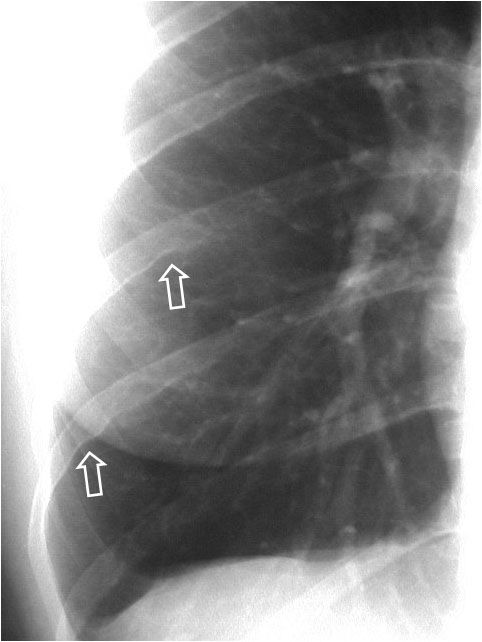

Signo de enfisema subcutáneo en la radiografía de tórax, que se ve como unas líneas radiolucentes que siguen la distribución de las fibras de los músculos pectorales mayores. En la imagen podemos verlo de forma bilateral (en la derecha se señalan con flechas). En esta misma radiografía pueden verse, además, signos de neumomediastino como el signo de la V de Naclerio y el signo de la V de las venas braquiocefálicas (ver el aparatado de Mediastino).

El nombre del signo viene dado por su parecido con las estriaciones que tienen las hojas de este curioso árbol. El Ginkbo biloba es el árbol más antiguo que existe, de forma que no tiene parientes cercanos en la clasificación taxonómica. Era conocida su existencia por restos fósiles y se pensaba que estaba extinguido. Un científico alemán en el siglo XVII lo encontró en Japón y lo trajo a Europa. En Japón es común encontrarlo en la proximidad de monasterios y era conocido por sus propiedades medicinales. Una curiosidad más es que un ejemplar de esta árbol situado a cerca de un kilómetro de donde cayó la bomba de Hiroshima, comenzó a rebrotar apenas un año después, por lo que allí es todo un símbolo de supervivencia y regeneración. Con esta breve historia no se nos olvida el valor de este signo.